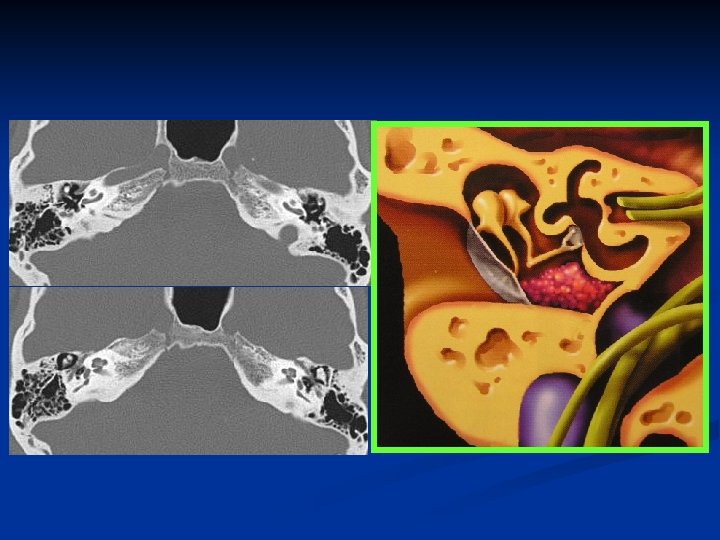

Ear n Keywords: -- Tympanic membrane, -- Ossicular chain (Malleus, Incus, Stapes) -- Facial nerve -- Cochlea, Semicircular canal -- External and internal auditory canals

Orbit n Keywords: -- Extraconal & Intraconal -- Lacrimal glands -- Muscles -- Superior & inferior orbital fissures -- Optic canal

Superior & inferior orbital fissures